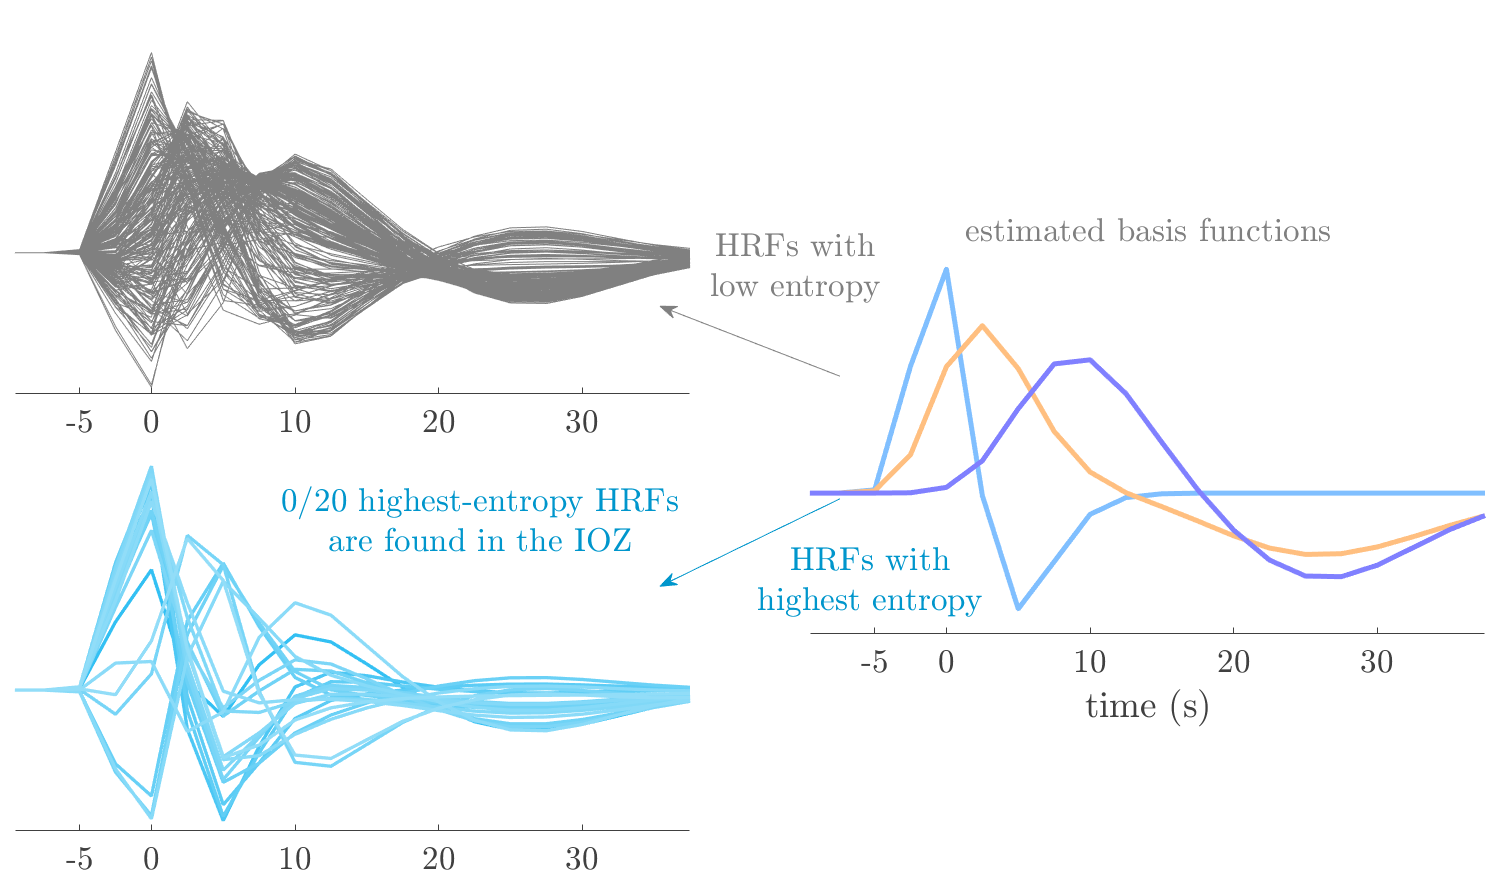

We analyze the solution with sources. Figure 1 shows the EEG signatures and HRF waveforms. One of the sources is highly correlated to the MWF reference (in grey), which was already known from Table B.3. This IED-related source had a typical low-frequency spectrum, which is expected for the typical spike-and-wave interictal discharges. The topography is relatively diffuse, although the highest amplitudes are mostly in the left hemisphere. This is in accordance with the lateralization of ictal onset zone (left temporal lobe, cfr. Table 1). There are some noteworthy observations to be made about some of the other components. The fourth has an unusually sharp spectrum, is mainly localized on two nonadjacent center electrodes, and is sustained for a single period of many seconds Hence, this component likely captured an artifact (of yet unknown origin), although we spotted no large-amplitude changes in the EEG itself. Similarly, the third source is only present at one frontal electrode, and exists in a frequency range above 20 Hz. It might represent a muscle artifact, e.g., due to frowning or twitching of some muscles in the forehead. The HRFs of all ROIs are shown in Figure 1(b). Two of the basis functions seem to have converged to a very similar waveform, which is an unfortunate possibility if two initial HRFs are too close to the same local optimum in their respective parameters. This reduces the expressive power of the basis set, which is clearly visible, since many ROIs have a nearly identical HRF. One of the twenty ROIs with the highest-entropy HRF overlapped the IOZ, although clearly this HRF (bold line) is not among the most dissimilar waveforms for this patient. This is also visible in Figure 2: both the HRF entropy and extremity maps show a small overlap with the delineated IOZ. Despite the good correspondence in the EEG domain, no significant (de)activation of the IED-component is found inside the IOZ.

We analyze the solution with sources, and show the results in Figure 3 and 4. As for patient 1, we found a source which is strongly correlated to the MWF envelope, and which had a mostly low-frequency behavior characteristic for spikes. The topography is mostly uninformative, and does not clearly correspond to the patient’s clinical data. The third source is mostly present at both sides of the head, is very sparsely active in time, and has a high-frequency content: this is most likely an artifact due to the neck muscles. Again, there is one of the highest-entropy HRFs which belongs to a ROI in the IOZ. Now, the waveform is clearly resolved from the other HRFs, through the strong initial dip (before 0 seconds). Such a dip is sometimes observed in HRFs, but its underlying physiological mechanism is not yet fully understood. It is possible that this dip reflects altered vascular autoregulation near the IOZ (cfr. the explanation in the Section 1 of the main text), or a rapid depletion in oxygen due to IED generation (before the IED becomes visible on the EEG). Figure 4 furthermore shows that the IED-related component is significantly active in parts of the IOZ, and deactive in others. As mentioned earlier, this deactivation may or may not be due to errors in sign correction. Interestingly, the ROI with the high alteration in neurovascular coupling is distinct from both the activated and deactivated ROIs.

We analyzed the solution with sources, and show the results in Figure 5 and 6. There is one source which is mostly correlated to the reference (but not extremely, see also Table B.3). This source had a right-temporal focus, conform the diagnosis in Table 1. The second source illustrates the phenomenon of an erroneous sign exchange between the spatial and spectral profiles. Also one of the HRFs has a negative polarity, which is a failure of the sign correction procedure (in this case, because there is exceptionally no positive overshoot). However, the HRF variability metrics are still interpretable, and indeed two ROIs among the ones with the highest-entropy HRFs overlap with the IOZ. The IED component is significantly active in a tiny portion of the IOZ (cfr. Figure 6). The second source is significantly active in symmetrical parts of the parietal lobe. Given its ongoing fluctuation over time, we hypothesize that this source captures a resting state network (RSN).

We analyze the solution with sources, and show the results in Figure 7 and 8. There is a clear IED-related component, with a very high correlation to the MWF reference, a typical spectrum, and an anterior-temporal focus, which corresponds very well to the patient’s diagnosis (cfr. Table 1). The fifth source seems present at only one channel, and has spectral harmonic at Hz and Hz. One of these peaks is reminiscent of the fourth component in patient 1. As Figure 8 shows, the HRF entropy and extremity prove to be strong biomarkers for the IOZ in this case, and also the significant IED activation and deactivation allow correct localization. In Figure 7, it is clear that some HRFs may still have the wrong sign, which means that the interpretation of ‘active’ and ‘deactivated’ is flipped in those ROIs. Hence, regions of significant deactivation are in fact significantly activated. The fourth source had a significant overlap with the auditory RSN, and its spectrum reveals activity in the band.

We analyze the solution with sources, and show the results in Figure 11 and 12. We found a clear IED-related component, with a characteristic spectrum and a topography which is backed up by the patient’s diagnosis (left anterior-temporal IOZ). The fourth source has a very similar topography and spectrum to the fifth source in patient 5. One HRF inside the IOZ had a high-entropy, and is distinguishable from the others by its very sluggish waveform, i.e., it is smeared out in time, with no sharp over- or undershoot. Also the pseudo t-map provided an accurate localization of the IOZ. Notably, in this patient, the extremity metric misses the deviating HRF in the IOZ (while the entropy metric picks it up). The second source overlapped with the frontal part of the default mode network (DMN), and is active in the and low bands.

We analyze the solution with sources, and show the results in Figure 17 and 18. The IED-related source had a high correlation with the MWF reference, but an odd bimodal spectrum. Its EEG topography is very consistent with the clinical description. Both HRF extremity and entropy are useful biomarkers for the IOZ. The IED activation and deactivation maps each had a very small overlap with the IOZ. The second source is temporally sparse and captures high-frequency EEG variations, which we identified as muscle artifacts.

We analyze the solution with sources, and show the results in Figure 19 and 20. Again we observe an IED-related source and a seemingly artifactual source with a spectral peak near 34 Hz. Many of the high-entropy HRFs are highly noncausal, and are associated to ROIs inside the IOZ. Hence, with both HRF metrics, the highest-scoring ROIs provides good localization of the HRF. While there are no significantly active ROIs in the IOZ, there are several significantly deactivated ROIs, which may indicate that the sign standardization was not done flawlessly (cfr. also some of the negative-peaking HRFs for patient 10). Surprisingly, the second source had one significantly active ROI, which overlaps with the IOZ, but which did not match its EEG topography. Hence, the nature of this source remains ambiguous.